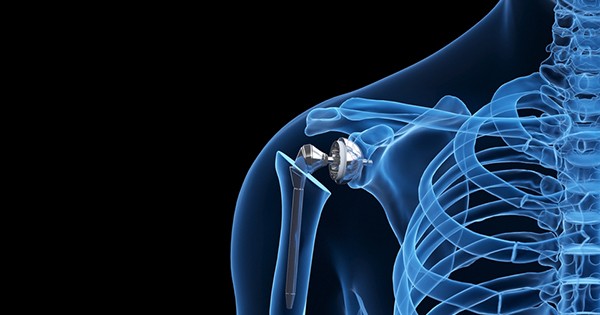

Reverse shoulder replacement is an advanced surgical procedure used to treat severe shoulder arthritis combined with rotator cuff damage. In a normal shoulder, the ball of the joint is at the top of the upper arm bone and fits into the socket of the shoulder blade. In this procedure, the structure is reversed—the ball component is attached to the shoulder blade, and the socket is placed on the upper arm bone. This design allows the deltoid muscle to power the arm instead of the damaged rotator cuff, helping restore movement and reduce pain.

This surgery is commonly recommended for patients with rotator cuff tear arthropathy, complex fractures, failed previous shoulder surgeries, or severe joint degeneration. An experienced Orthopedic surgeon in Guntur carefully evaluates imaging tests, pain levels, and mobility before suggesting this procedure. Consulting a qualified Orthopedic doctor ensures accurate diagnosis and a personalized treatment plan based on the patient’s age, activity level, and overall health.

The surgery is performed under anesthesia and typically takes a few hours. After surgery, patients undergo structured rehabilitation to regain strength and flexibility. Choosing a well-equipped Orthopedic hospital in Guntur is important for safe surgery, advanced technology, and comprehensive post-operative care. With proper treatment and physiotherapy, most patients experience significant pain relief and improved shoulder function, enabling them to return to daily activities with better comfort and mobility.